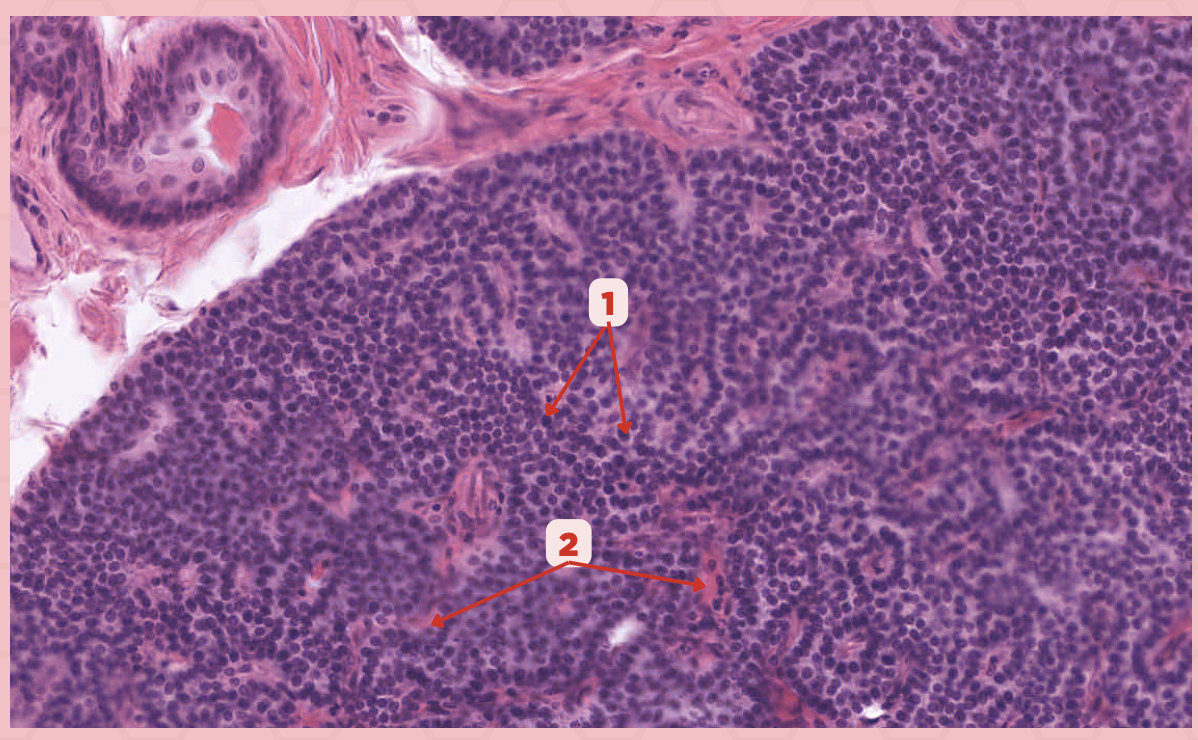

Parathyroid

Identify the specimen.

Chief Cells

Identify the structure labeled as 1. This comprise the majority of cells in the parathyroid gland.

Septa

Identify the structure labeled as 2.

Parathyroid hormones

What hormones are synthesized and secreted by the cell in Pointer #1?

Parathyroid

Identify the specimen.

Chief Cells

Identify the specimen labeled as 1.

Oxyphil Cells

Identify the specimen labeled as 2.

Adipocytes

Identify the specimen labeled as 3.

Capillaries

Identify the specimen labeled as 4.

Newborns

Pointer #2 is hardly present in the parathyroid glands of _____.